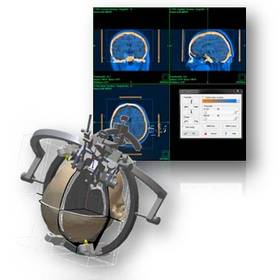

inomed Planungssoftware iPS

Moderne bildgebende Verfahren in Kombination mit den Entwicklungen im Bereich der elektronischen Datenverarbeitung verhalfen der stereotaktischen und funktionellen Neurochirurgie zum Durchbruch. Denn erst sie ermöglichten präzise und gewebeschonende Eingriffe wie zum Beispiel die Tiefe Hirnstimulation (THS) am menschlichen Gehirn.

Die visuelle Planung einer Operation am Gehirn ist in der Stereotaxie >> unerlässlich für einen sicheren und zielführenden Eingriff, dies gilt im Besonderen für die THS. Die Vorbereitung eines Eingriffs – ob THS oder stereotaktische Biopsie – mittels des inomed Planungssystems iPS ist dabei der erste Schritt für Neurochirurgen, um patientenschonende und lebenserhaltende Therapiemöglichkeiten zu realisieren.

Die hohe Qualität der Bilddarstellung zeichnet das inomed Planning System (iPS) aus. Die automatische Zusammenführung verschiedener Bildmodalitäten ermöglicht eine schnelle und sichere Verifikation der geplanten Zugänge. Diese Zugänge sind für eine erfolgreiche THS zwingend notwendig. Auf Wunsch lassen sich anatomische Atlanten über patientenbezogene Daten projizieren. Dies erlaubt wiederum die Verifikation anhand anatomischer Grundlagen.

Die Planungssoftware iPS von inomed unterstützt sämtliche Planungsansätze, ob „freehand“, funktionell, atlasbasiert oder metabolisch orientiert. Hierfür stehen jeweils verschiedene Möglichkeiten zur Verfügung, die einander ergänzen können. Auch die Option einer Vorabplanung mit Übertragung auf die stereotaktische Bildmodalität gewährleistet die rasche aber genaue Zielpunktplanung am Tag des Eingriffs (THS, Biopsie etc.).

Die Möglichkeit einer schnellen Generierung von 3D Ansichten des Patientenschädels hilft bei der Verifikation der Zielpunktplanung im Zuge der THS. Durch Projektion des verwendeten Stereotaxie-Systems bekommt der Anwender eine realistische Darstellung über Anordnung und Auswirkung der Trajektorie-Planung auf den Systemaufbau.